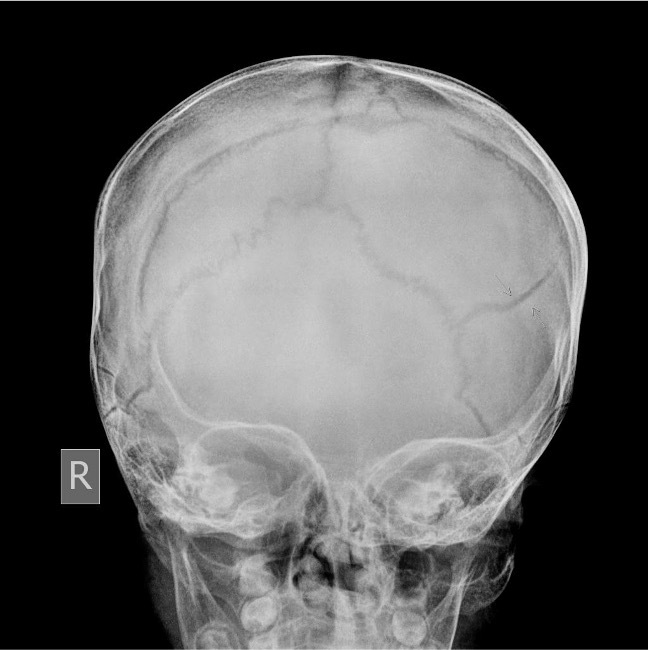

Fracture in left parietal bone with fracture under scalp

Patient presenting with hypercalcaemia

Multiple osteolytic lesions secondary to multiple myeloma Also know as 'rain-drop skull'